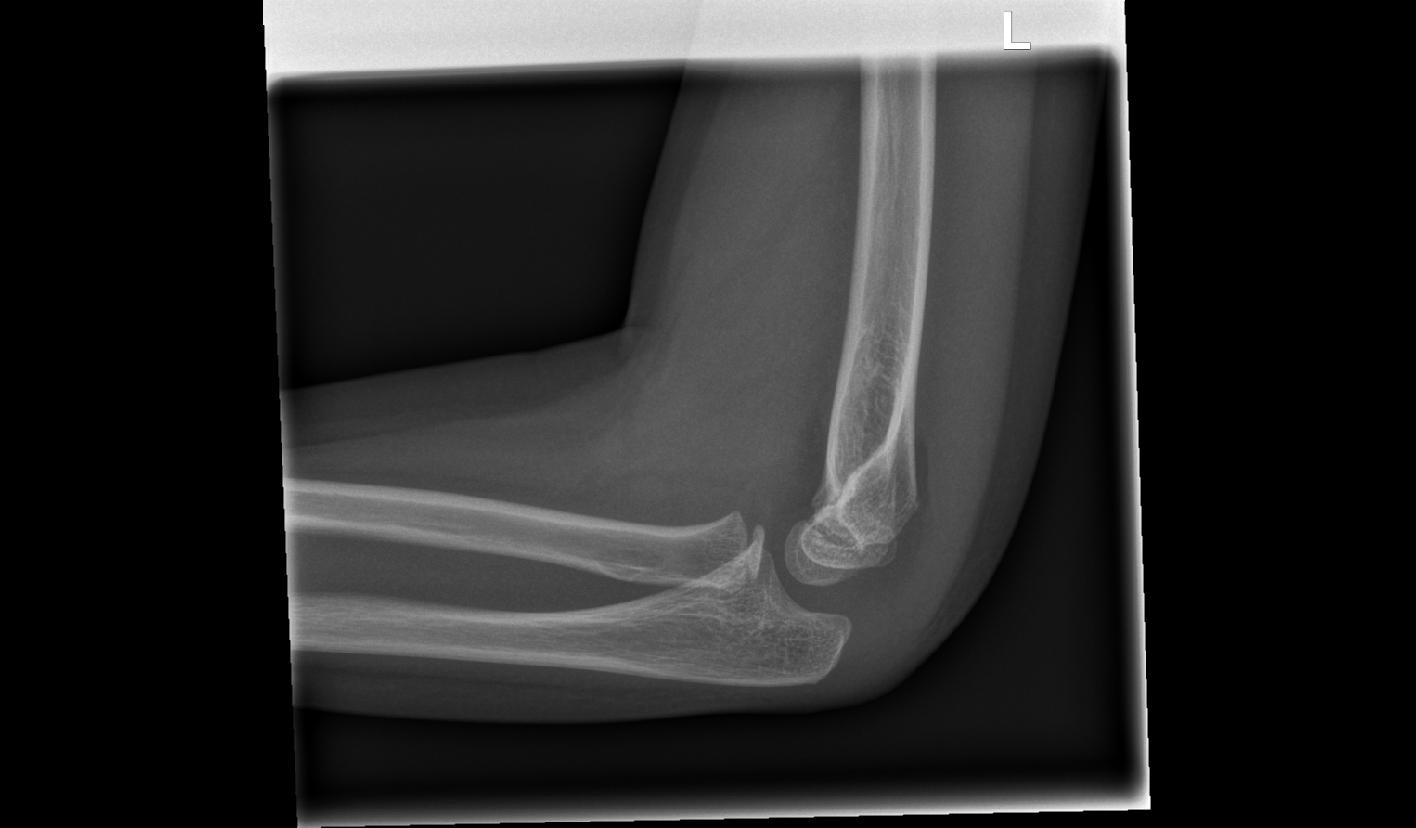

AI-Elbow

Automated Identification and Management Guidance of Pediatric Elbow Fractures

CT-Elbow

Computed Tomography (CT) for occult fractures from the elbow in children.